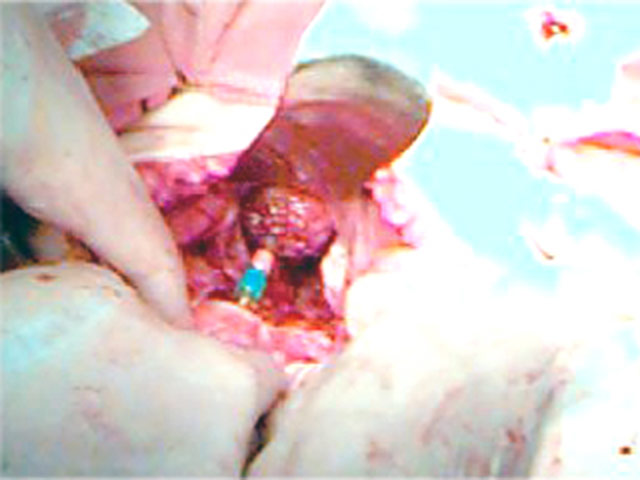

Carcinoma de Reto

Vemos reto dissecado profundamente

na pelves Tumor há 8cm da linha pectínea.

Reto aberto, já ressecado o tumor,

com o grampeador endoluminal passado.